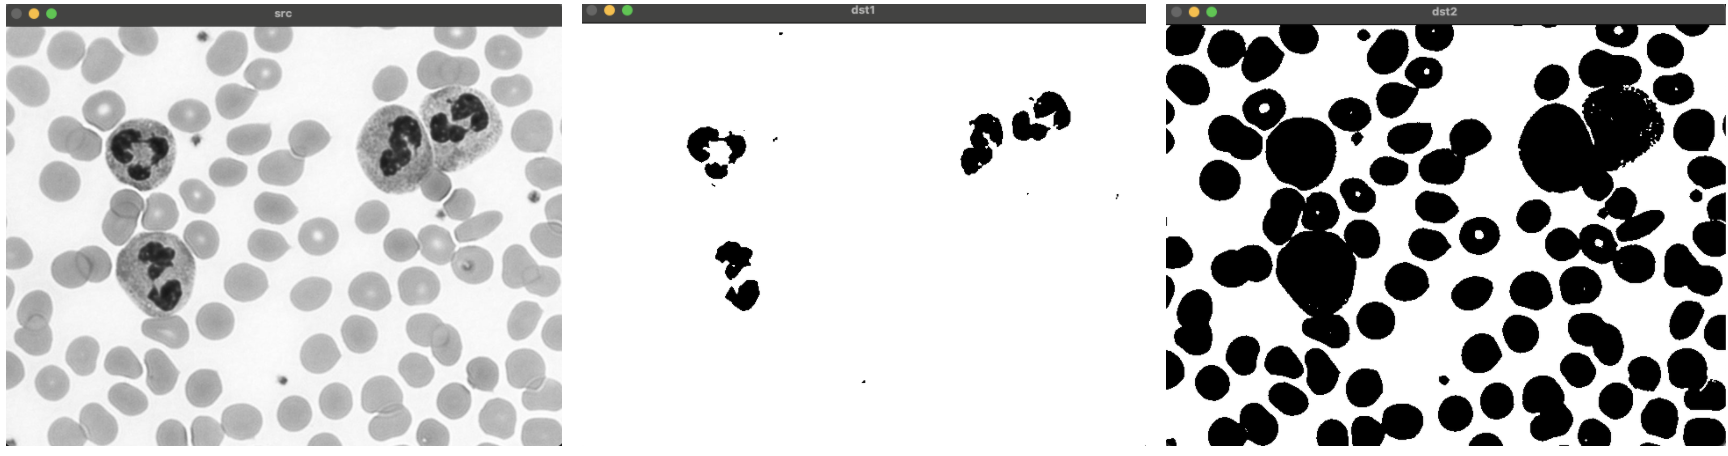

src = cv2.imread('cells.png', cv2.IMREAD_GRAYSCALE)

_, dst1 = cv2.threshold(src, 100, 255, cv2.THRESH_BINARY)

_, dst2 = cv2.threshold(src, 210, 255, cv2.THRESH_BINARY)

cv2.imshow('src', src)

cv2.imshow('dst1', dst1)

cv2.imshow('dst2', dst2)